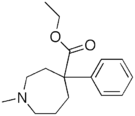

4-Phenylpiperidines

Pethidines (meperidines)

Structures